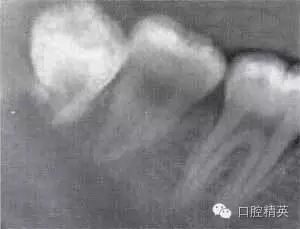

圖6-4 以上類型的下頜第三磨牙由于根阻力大,一般需要分根才能拔除

A.多根牙 B。超長根 C。牙根向遠(yuǎn)中彎曲 D。兩根環(huán)抱 E。根分叉大 F,根端肥大 G。彎根 H.U型根(X線片及離體牙)